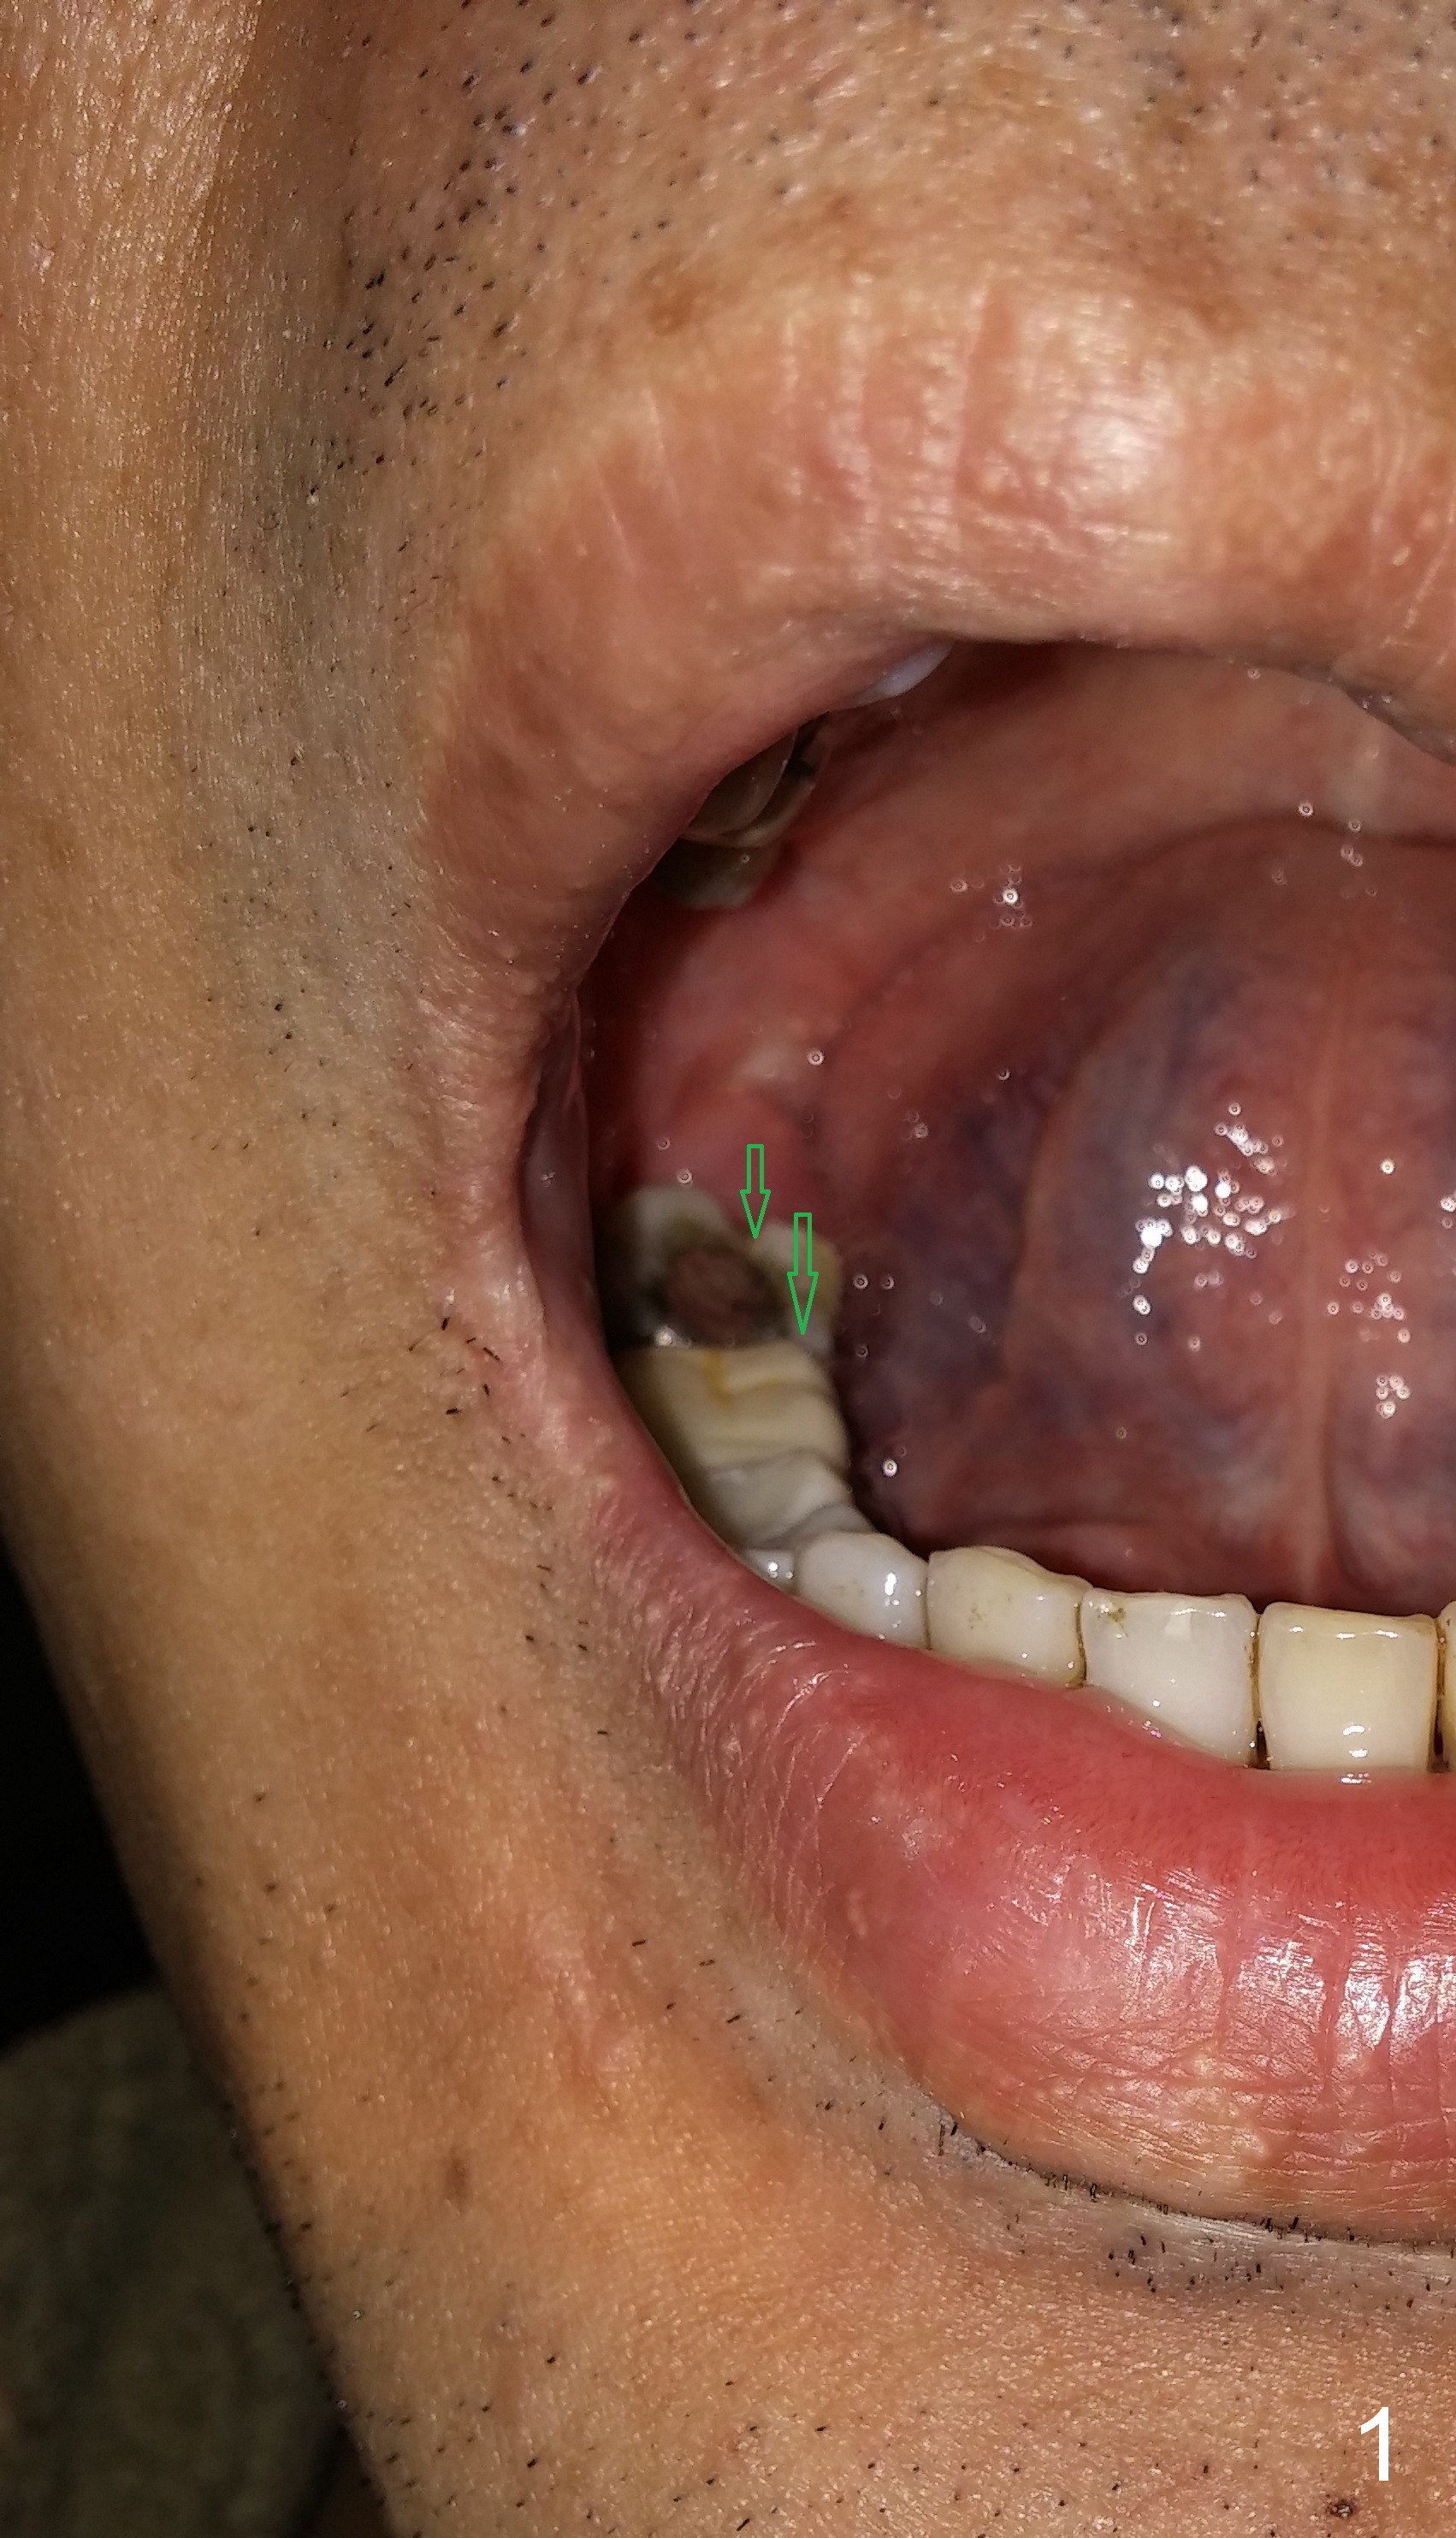

A 39-year-old man (ZC) fractures the lingual portion of the tooth #31 while eating peanut during Christmas (Fig.1 green arrows), a few months finishing #28,29 implant crowns. It fractures between the large amalgam (Fig.3 A) and the lingual portion of the tooth (L). It should be subgingival and nonsalvageable. Prepare crown prep or immediate implant. If the latter is indicated, the socket will be treated with 2% Xylocaine/1:50,000 Epinephrine. The distance between the apex of the socket and the Inferior Alveolar Canal is >5 mm (Fig.2,4). If osteotomy is controlled 3 mm beyond the apex of the socket, it is safe (Fig.3,5). A 5.9x10 or 12 mm implant should be able to engage to the buccal and lingual walls for additional stability (Fig.5), while there will be mesial and distal gaps to be filled with bone graft (Fig.3 red dots).

A 6 mm implant is indicated in the lower 2nd molar socket when there is no infection with enlarged socket. Oversized implants (7,8 mm) may invade the buccal plate.